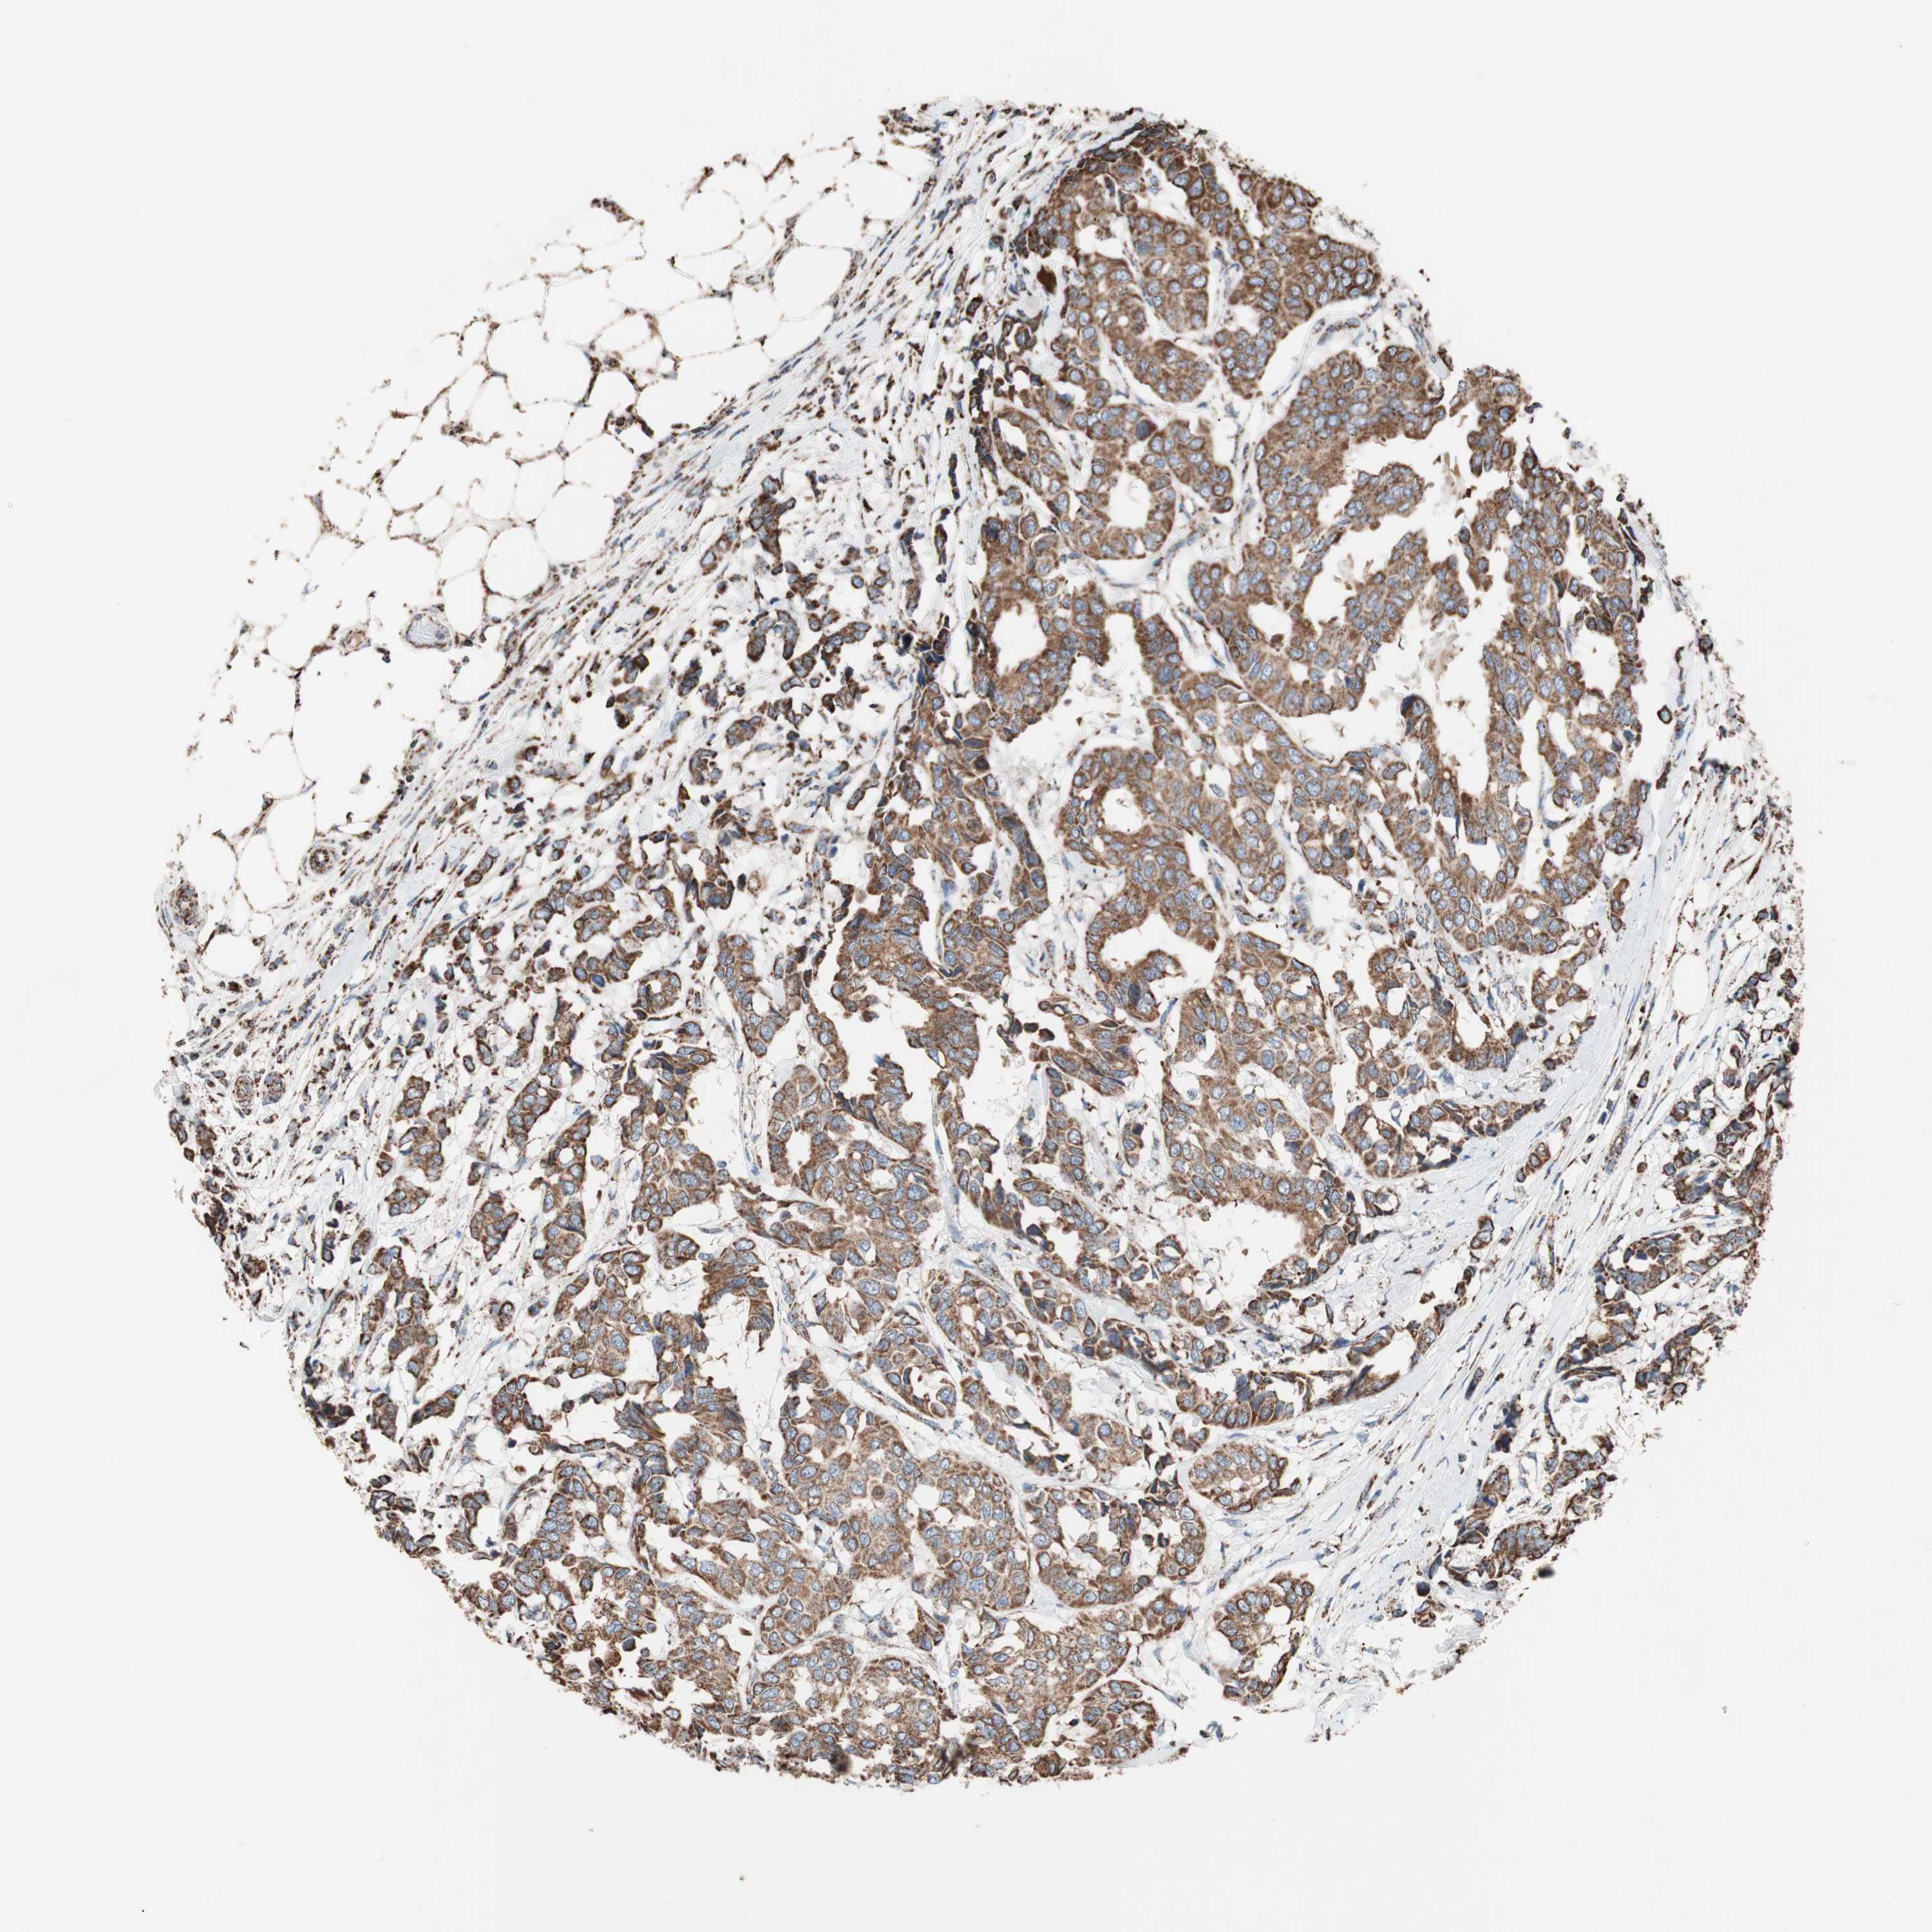

CANCER BREAST CANCER Show tissue menu

BRCA TCGA BRCA VALIDATION PROTEIN EXPRESSION

ANTIBODIES

AND

VALIDATION